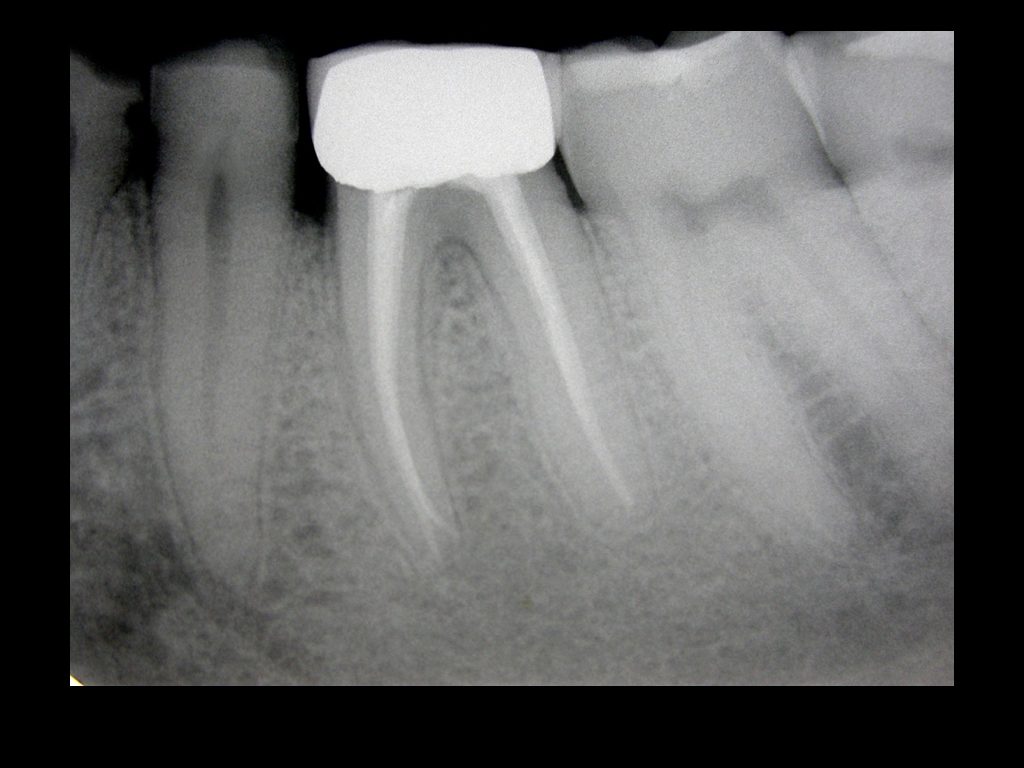

D’accordo col paziente viene effettuata la terapia canale che rimuove i batteri causa dell’infezione dall’interno del dente (immagini 2-3).

Nei successivi controlli a distanza, si nota la completa guarigione con scomparsa della radiotrasparenza..( assenza di aree “nere”).(immagine 4)